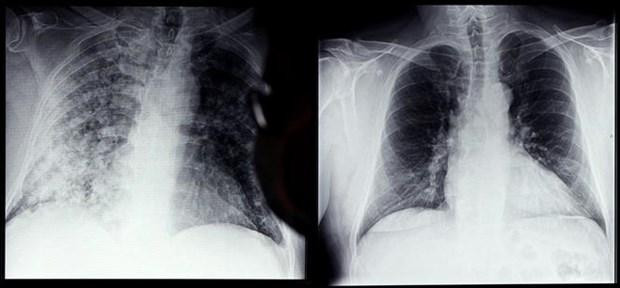

| Phim chụp Xquang phổi của bệnh nhân COVID-19 (trái) và phổi của người bình thường tại bệnh viện ở Magdeburg, miền đông nước Đức, ngày 28/4/2021. (Ảnh: TTXVN) |